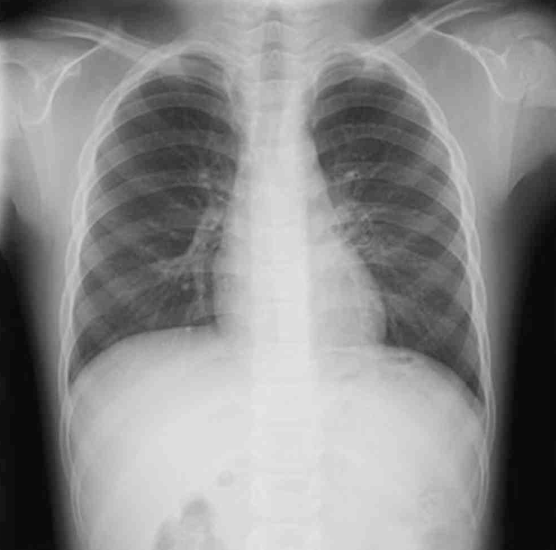

5세 남아가 3주 동안 기침을 계속하여 병원에 왔다. 맥박 70회/분, 호흡 18회/분, 체온 36.8°C이다. 후비루가 보이고 호흡음은 정상이다. 가슴 X선사진과 부비동 X선사진이다. 진단은?

CXR: 정상

• 신체 진찰에서 후비루가 관찰되며, 가슴 청진에서 호흡음은 정상이다. 또한, CXR에서도 정상 소견이 확인되어 하부 호흡기 질환의 가능성은 낮다.

• 폐렴: 발열, 호흡곤란, 수포음 등 청진 소견과 함께 가슴 X선에서 폐 침윤 소견이 관찰된다. 본 환아는 발열, 호흡곤란 등 특징적인 폐렴 증상이 없으며, X선에서도 이상 소견이 없어 폐렴과 거리가 멀다.